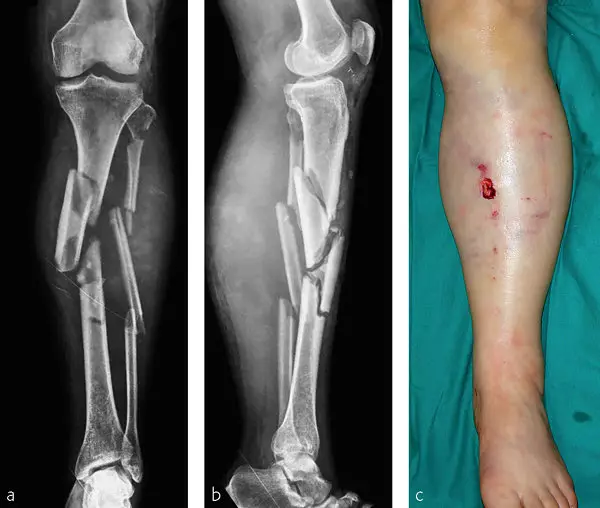

The fall ended her Olympic campaign. She was treated on the slope before being airlifted to hospital. Doctors later confirmed she had sustained a complex fracture of the tibia, the main bone in the lower leg.

A sports medicine expert explained that this type of fracture is considered severe. In some cases, surgeons use an external fixator — a stabilizing frame placed outside the leg — to hold the bone in position while it heals. Such injuries often require more than one operation and a lengthy rehabilitation.